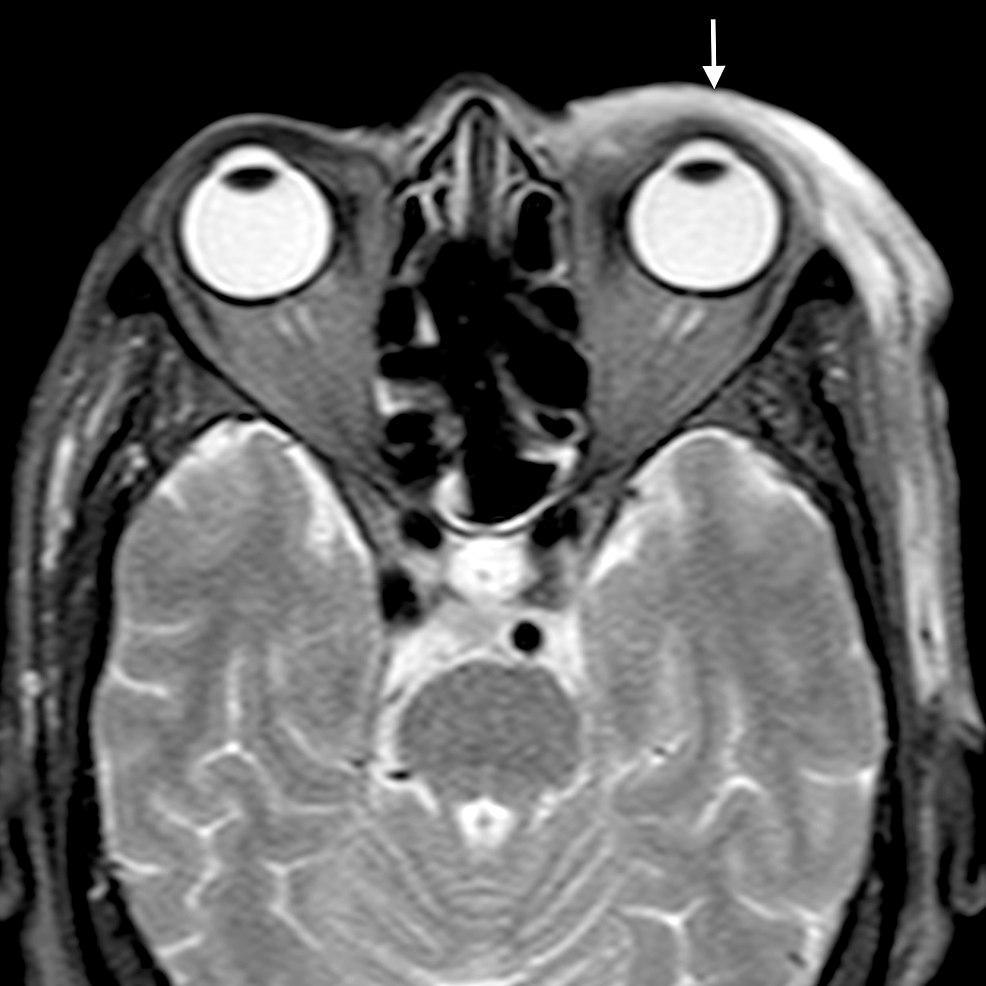

The main complications of orbital cellulitis (Figures 2-4) encountered in our study were:

1. An orbital abscess (Figures 5-6);

2. Preseptal cellulitis and abscess (Figures 7-8);

3. Periorbital cellulitis (Figures 9-10);

4. Dacryoadenitis (Figures 11-12);

5. Optic neuritis/perineuritis (Figure 13);

6. Cavernous sinus thrombophlebitis and thrombosis (Figure 14).

The most common complication of orbital cellulitis was orbital/periorbital abscess formation (eight cases, 53.3%), followed by optic neuritis (four cases, 26.67%), intracranial involvement (four cases, 26.67%), dacryoadenitis (three cases, 20%) and cavernous sinus thrombophlebitis (three cases, 20%).